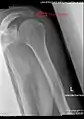

Radiograph of the shoulder showing an os acromiale